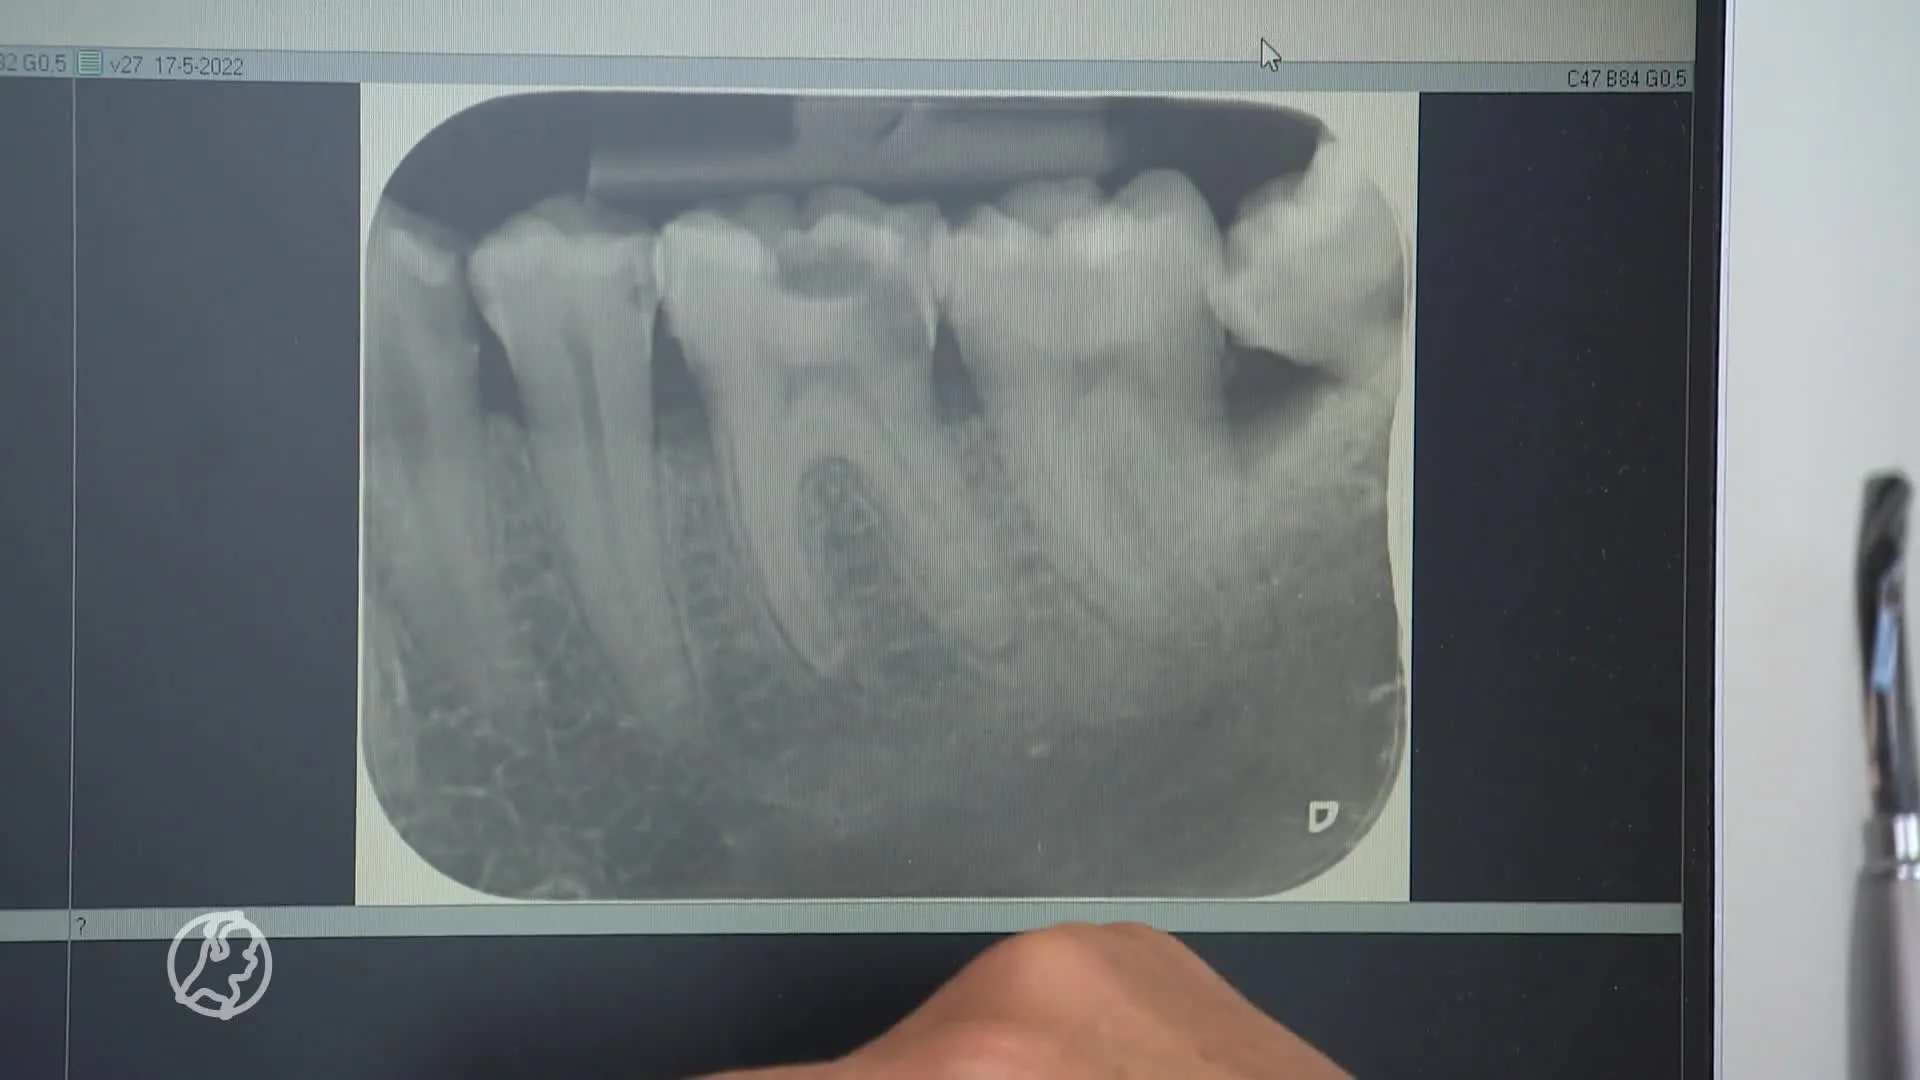

Ouderen lopen te lang rond met problemen aan hun tanden, waarschuwt de Organisatie van Nederlandse Tandprothetici. Voorzitter Marnix de Romph zegt dat mensen soms 10 tot 20 jaar lang hetzelfde kunstgebit gebruiken.

Het gaat dan bijvoorbeeld om "een kunstgebit dat inmiddels niet meer goed past of pijnplekken geeft. Dat geeft weer problemen met kauwen en dus met eten, waardoor de algehele gezondheid achteruit kan gaan".

Volgens de vereniging hebben ongeveer 3 miljoen mensen in Nederland een geheel of gedeeltelijk kunstgebit, van wie de meesten 65 jaar of ouder zijn. De beroepsorganisatie van kunstgebittenmakers roept "familieleden, mantelzorgers, kennissen, buren en zorgverleners" op om kwetsbare ouderen in de gaten te houden en te helpen.